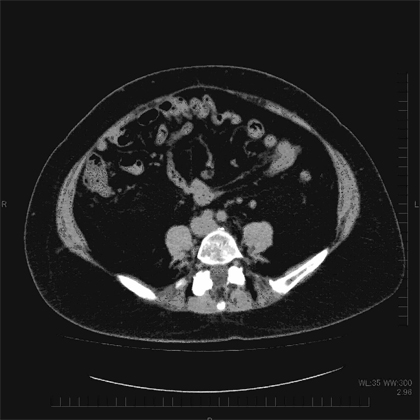

体脂肪には、皮下脂肪と内臓脂肪の2種類があります。指でつまめるのが皮下脂肪、体の奥に隠れているのが内臓脂肪で、それぞれのタイプを皮下脂肪型肥満、内臓脂肪型肥満と呼びます。

内臓脂肪は、わりと最近になってから存在が確認されました。CTスキャンが実用化し、体を輪切りにした画像が容易に得られるようになったからです。こうして画像で見ると、違いは一目瞭然ですね。

一般的には、内臓脂肪はつきやすく取れやすい、皮下脂肪はつきにくいが取れにくいという傾向があります。

内臓脂肪型肥満